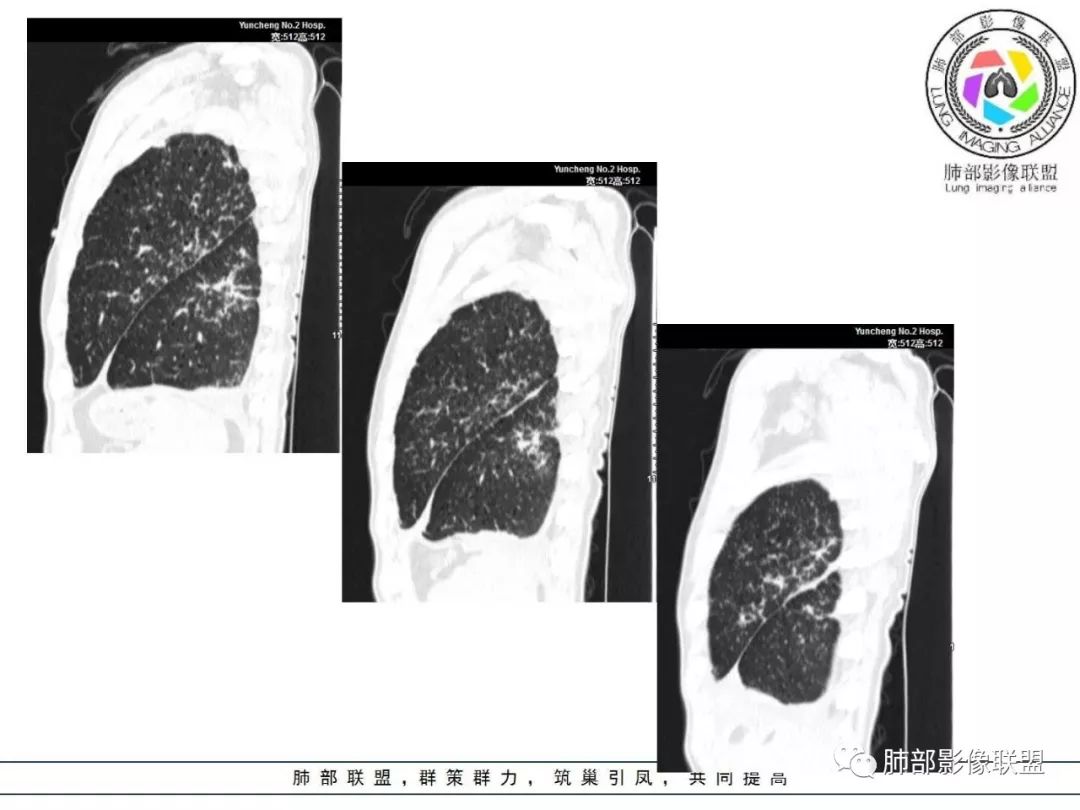

双肺间质性病变,中央间质增厚,胸膜下间质增厚,左侧胸膜肥厚,胸廓变小,肋间隙变窄。

胸部CT:两肺弥漫病灶,磨玻璃影,少许实变,部分累及胸膜,磨玻璃区可见囊?少许胸腔积液,两肺可见结节,支气管血管束增粗,小叶间隔增厚,支气管走形有扭曲扩张,可见纤维化。气肿、大泡。考虑:感染性病变,PCP?查下HIV,CD4,G等。鉴别结核、结缔组织病肺浸润。

55多男性,发热为主诉,体温38℃-39℃多,午后及夜间发热为主,峰值40℃,伴黄痰,CRP高,血糖正常,胸部CT:两肺弥漫病灶,磨玻璃影,少许实变,部分累及胸膜,两肺可见结节,似可见树芽,支气管血管束增粗,小叶间隔增厚,见肺气肿、大泡。考虑感染性病娈,肺结核可能性大。

患者中年男性,发热1月,体温38℃-39℃,峰值40℃,无畏寒、寒战,伴黄痰,CRP升高明显,降钙素原稍升高,血沉、血糖正常。胸部CT:两肺弥漫病变,磨玻璃影+点片渗出,部分累及胸膜,磨玻璃区边界清楚,少许胸腔积液,两肺支气管血管束增粗,小叶间隔增厚,部分支气管走形有扭曲扩张,可见肺气肿、右肺尖肺大泡及部分纤维化改变。综合考虑:感染性病变。结核或PCP可能性大,鉴别风湿免疫、结缔组织疾病肺浸润和腺癌等恶性病变。

胸部CT:两肺弥漫病灶,中央间质分布为主,部分位于胸膜及叶间裂旁,磨玻璃影,斑片影,部分实性结节,肺气囊,支气管血管束增粗,小叶间隔增厚,叶间裂不均匀增厚,支气管走形有扭曲扩张,可见纤维化、气肿、大泡。考虑:LIP加MALT。鉴别PLCH、PCP、结核、结缔组织病肺浸润。

病灶呈片状磨玻璃密度影,呈典型的烟花征。磨玻璃影密度偏高,有网结节样改变,与正常肺实质分界清楚,且常见相对高密度的勾画。

烟花征分为3肿类型:晕征、反晕征及均匀分布。

病变一般沿血管支气管束分布或小叶分布,一般上肺多于下肺(这与常见继发性肺结核分布相若)。

常会伴有其他继发性肺结核病灶,如斑片影、结节影,树芽征,新旧不等改变。

2. 肺气肿背景(小叶中心性肺气肿);双肺多发病灶整体沿血管支气管束及胸膜下分布,以上叶及下叶背段分布为主,有实变及GGO,边界清楚,有树芽,小叶间隔及中央间质增厚,叶间裂见到多发结节,部分支气管不规则牵拉扩张,提示病灶纤维化明显,结合临床病史,考虑病灶为间质性感染,肺门及纵隔内有钙化淋巴结,小叶间隔结节,考虑淋巴道增值性疾病可能,综合常规要怀疑间质性肺结核。